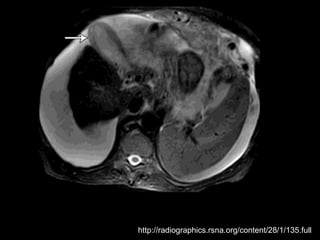

Colecistite Xantogranulomatosa

Forma pouco comum de colecistite crônica;

Quase sempre associada a cálculos e a graus

variados de fibrose;

Patogênese incerta, entretanto, foi sugerido que a

presença de úlceras na mucosa ou a ruptura dos

seios de RA, juntamente com a obstrução do fluxo

de saída por cálculos biliares e infecção, levam a

bile a penetrar na parede da VB e a formar

xantogranulomas

Na TC:

Os cálculos biliares e o espessamento irregular

semelhante a uma massa da parede da VB são as

anormalidades mais comuns.

Vários estudos relataram que os nódulos

hipoatenuantes intramurais vistos na TC

representam uma lesão xantogranulomatosa, um

abscesso ou a combinação de ambos;

Realce da superfície luminal(70%) correspondia à

presença de uma camada epitelial.

O radiologista deve distinguir entre a colecistite

xantogranulomatosa e o carcinoma da vesícula

biliar

Linha de mucosa evidente

Realce da superfície luminal

Nódulos intramurais hipoatenuantes(TC) ou com

sinal alto(RM T2)

Colecistite Xantogranulomatosa Forma pouco comum de colecistite crônica; Quase sempre associada a cálculos e a graus variados de fibrose; Patogênese incerta, entretanto, foi sugerido que a presença de úlceras na mucosa ou a ruptura dos seios de RA, juntamente com a obstrução do fluxo de saída por cálculos biliares e infecção, levam a bile a penetrar na parede da VB e a formar xantogranulomas

Colecistite Xantogranulomatosa Na TC: Os cálculos biliares e o espessamento irregular semelhante a uma massa da parede da VB são as anormalidades mais comuns. Vários estudos relataram que os nódulos hipoatenuantes intramurais vistos na TC representam uma lesão xantogranulomatosa, um abscesso ou a combinação de ambos; Realce da superfície luminal(70%) correspondia à presença de uma camada epitelial.

Colecistite Xantogranulomatosa O radiologistadeve distinguir entre a colecistite xantogranulomatosa e o carcinoma da vesícula biliar Linha de mucosa evidente Realce da superfície luminal Nódulos intramurais hipoatenuantes(TC) ou com sinal alto(RM T2)